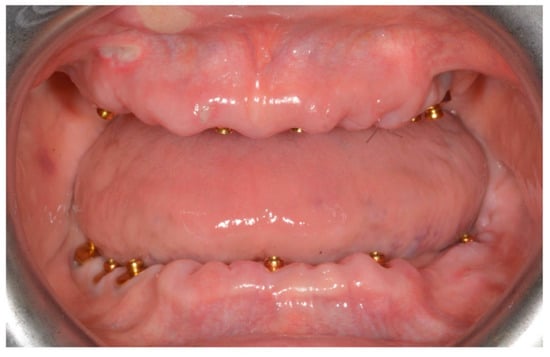

- Bleeding index and plaque index were evaluated in six sites around each implant–abutment interface at the one-year examination with a periodontal probe (PCPUNC156, Hu-Friedy, Milan, Italy). One dental hygienist at each center, not previously involved in this study, performed the periodontal measurements

| OT Bridge in the mandible arch | Poor oral hygiene (Bleeding on Probing > 25%) |

| Bleeding on probing | 8.9% | ||

| 5.8% | |||